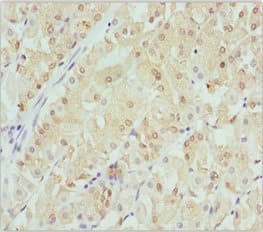

Anti-Beta crystallin S antibody(ab229949)

Rabbit Polyclonal Beta crystallin S antibody. Suitable for WB, IHC-P and reacts with Mouse, Human samples. Immunogen corresponding to Recombinant Full Length Protein corresponding to Human CRYGS.

Applications IHC-P, WB